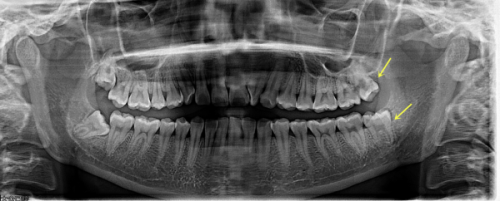

上海鼎植傅思维全瓷牙实例

患者张女士,因牙齿颜色不美观且有轻微缺损,影响了面部美观和自信心。傅思维医生为她进行了详细的口腔检查和沟通后,制定了全瓷牙修复方案。在治疗过程中,傅医生操作精细,每一个环节都严格把控。更终,张女士戴上了全瓷牙,牙齿变得洁白整齐,笑容更加自信。张女士对治疗成效非常满意,称赞傅医生技术不错,服务周到。